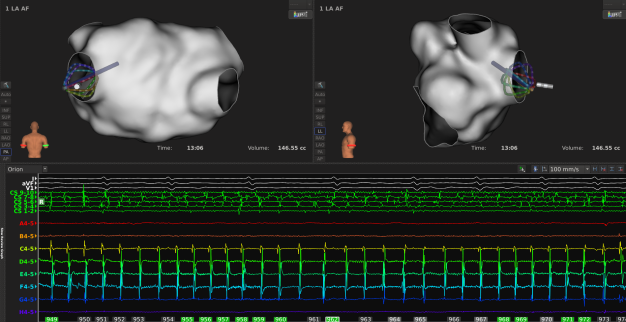

手术过程:

ABL strategy:CPVI+顶部线+后壁底部线+MVI

导管移动或贴靠不稳定时,LI曲线波动剧烈,实时LI数值变化较大;

消融过程中LI稳定下降,通常5-8s到达平台期;

2

到达平台期后,最大LI下降值通常在15-25Ω范围内,提示消融有效;

3

消融过程中也要结合电位判断消融效果,通常阻抗下降至平台期后,MiFi微电极电位下降或消失明显,继续放电5s;

4

不同部位LI下降值不同,且初始阻抗越高,消融过程中阻抗下降就越明显;

5

LI值还可以提示心肌的健康程度,低电压区及疤痕区组织,基础LI要明显低于健康心肌,仅比血池略高约5Ω,有时甚至会低于血池阻抗;消融过的心肌(二次贴靠)LI值较首次会更低,大概在90Ω左右;